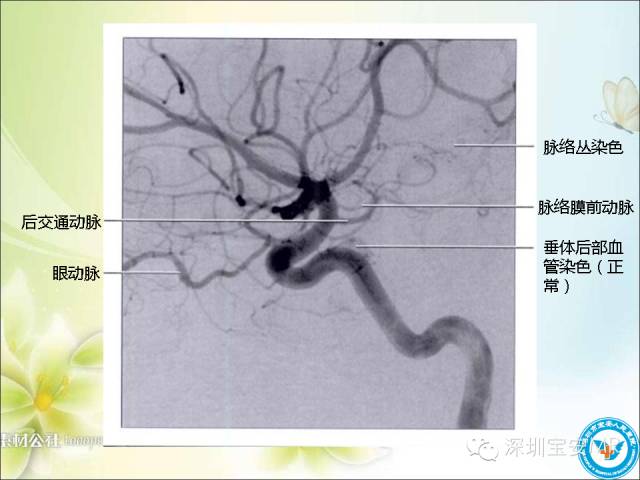

看了这么多,先来一段血管TOF的原始图像视频,对于了解颅内动脉走形及3D很有帮助的!